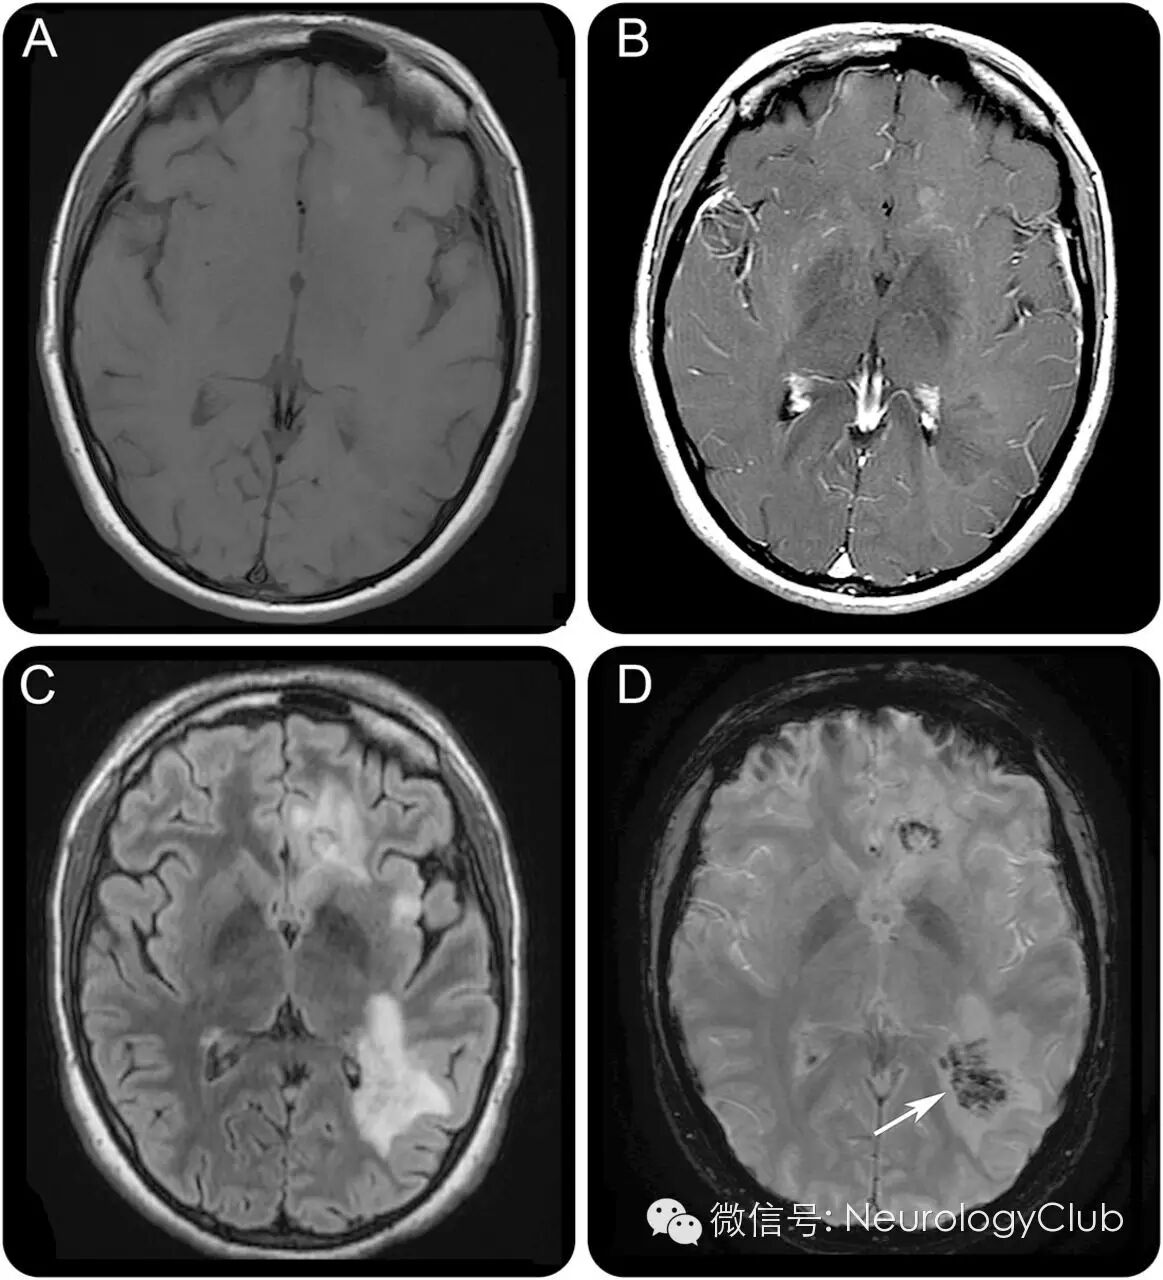

女性,24岁,表现为缓慢进展的意识状态改变伴发热。头颅MRI提示多发颅内占位性病变。T2* MRI上典特征性的血管分支形态是判断这一肿瘤样病灶为血管来源的关键(图1 D)。

(图1:本例继发性中枢神经系统血管炎的影像学表现。A:T1WI;B:T1+C;C:FLAIR;D:T2*上位于中心的分支引流静脉符合充盈/血栓形成的小静脉/小静脉炎,是识别血管性病因并与肿瘤鉴别的关键)

中枢神经系统血管炎可表现为颅内肿瘤样病灶。T2* MRI可见静脉分支是其与脑肿瘤鉴别的关键(图1 D,图2 D)。